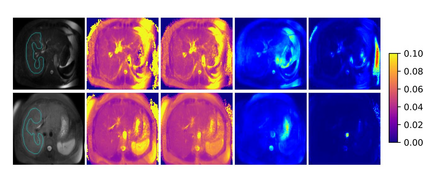

$T_{1\rho}$ mapping is a promising quantitative MRI technique for the non-invasive assessment of tissue properties. Learning-based approaches can map $T_{1\rho}$ from a reduced number of $T_{1\rho}$ weighted images, but requires significant amounts of high quality training data. Moreover, existing methods do not provide the confidence level of the $T_{1\rho}$ estimation. To address these problems, we proposed a self-supervised learning neural network that learns a $T_{1\rho}$ mapping using the relaxation constraint in the learning process. Epistemic uncertainty and aleatoric uncertainty are modelled for the $T_{1\rho}$ quantification network to provide a Bayesian confidence estimation of the $T_{1\rho}$ mapping. The uncertainty estimation can also regularize the model to prevent it from learning imperfect data. We conducted experiments on $T_{1\rho}$ data collected from 52 patients with non-alcoholic fatty liver disease. The results showed that our method outperformed the existing methods for $T_{1\rho}$ quantification of the liver using as few as two $T_{1\rho}$-weighted images. Our uncertainty estimation provided a feasible way of modelling the confidence of the self-supervised learning based $T_{1\rho}$ estimation, which is consistent with the reality in liver $T_{1\rho}$ imaging.